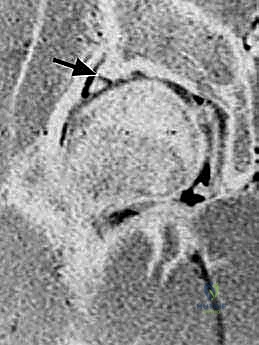

- الأشعة المقطعية ثلاثية الأبعاد (3D CT Scan): تُستخدم أحياناً للتخطيط الجراحي الدقيق وتشكيل نموذج ثلاثي الأبعاد للتشوهات العظمية.